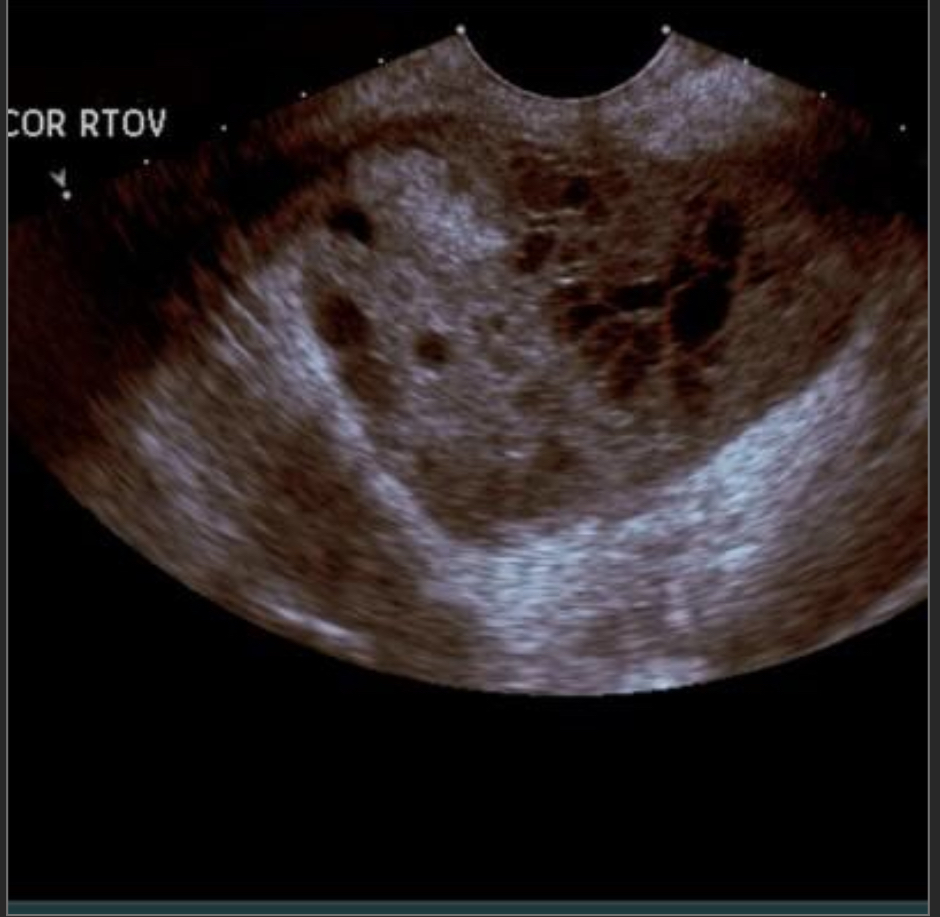

24 year old female with pelvic pain

Turbo-ovarian abscess

complex fluid next to the ovary w/appropriate history